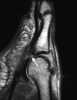

Chronic joint effusion